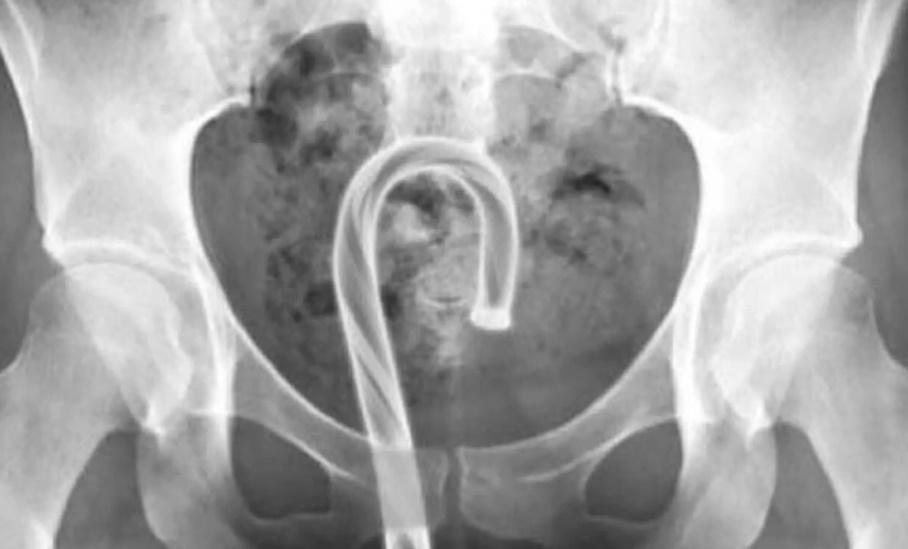

下體卡士的糖,英女醫生籲勿將聖誕飾物當性用具。(網上圖片)

聖誕節將至,不少家庭會購買聖誕飾物裝飾家居,然而英國1名女醫生近日卻發現,愈來愈多人喜歡把聖誕飾物當成性用具使用,甚至有女病人竟不小心將極具聖誕標誌的士的糖塞進下體卡著,她警告,由於士的糖屬於易碎物,不但難於移除,還有可能造成下體嚴重感染。

綜合報道,婦科女醫生Sarah Welsh近日應診時發現,聖誕裝飾品卡在下體的個案突然大增,令她決定出面呼籲大眾:「將聖誕飾物塞進下體是不可取的行為」,當中更有士的糖、裝飾球卡布陰道的個案。Sarah Welsh語重深長勸說:「任何含糖份的物件都應該遠離陰道,除了糖果易碎容、易折斷,糖製品也有可能破壞陰道內微生物環境,導致私處感染」。她又指,裝飾品表面亦可能鋒利或有碎片,容易弄傷下體,導致使用者疼痛或是受傷。